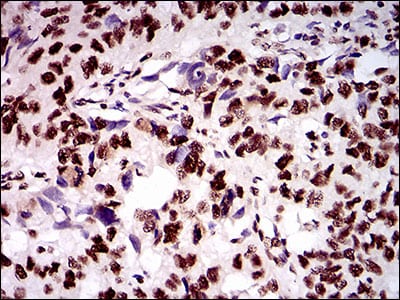

- Immunohistochemical analysis of paraffin-embedded human colon cancer tissues using KIAA1967 mouse mAb with DAB staining.

- Immunohistochemical analysis of paraffin-embedded human esophageal cancer tissues using KIAA1967 mouse mAb with DAB staining.